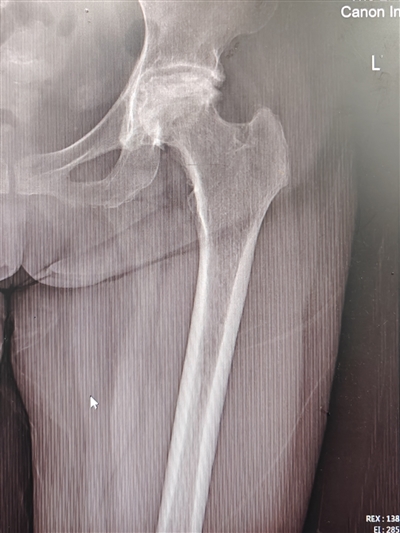

56岁的黎女士(化名)双侧髋关节反复疼痛、活动障碍一年多了,期间曾在多家医院就诊,但医生均拒绝为其进行手术治疗,保守药物对症治疗效果也不佳。由于疼痛剧烈、长期夜间无法入睡,黎女士逐渐产生了抑郁的情绪,甚至有了轻生的念头。在辗转求医的过程中,黎女士经朋友介绍,带着仅有的希望找到了重庆医科大学附属第二医院骨科—关节外科中心的李锐冬副主任医师,李锐冬副主任医师仔细询问病史后,发现黎女士因患有皮肌炎长期使用激素,结合影像学检查,确定黎女士为双侧股骨头坏死。

李锐冬副主任医师团队立即对黎女士进行了全面的检查,发现其双侧髋关节病变均较为严重,需进行全髋关节置换。传统的后外侧入路切口比较长,考虑到患者本身肥胖,且有皮肌炎病病史,传统入路更易导致脂肪液化、伤口愈合不良等问题,结合到患者希望术后康复周期尽量短等意愿,李锐冬副主任医师团队在经过严密的讨论、多学科会诊及与患者仔细的沟通后,决定对黎女士行创伤更小、康复更快的DAA全髋关节置换术。

术前X片